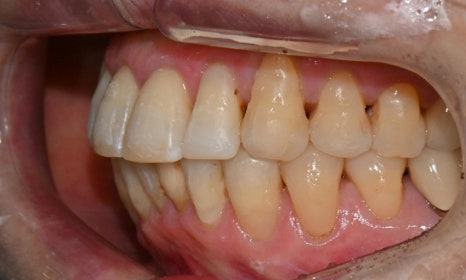

본 환자는 70세 여환으로 가만히 입을 다물고 있을 때 화난 것 처럼 보인다고 해서 튀어나온 앞니를 조금 넣고 싶다는 주소로 내원하셨습니다. 전체적인 치아 및 잇몸 상태를 검진해본 결과, 마모되어 깨진 치아도 있었고, 치경부(치아와 잇몸 사이 경계 부위)가 마모되어 파여 있는 부위도 많았습니다.

2025.2.3. 초진